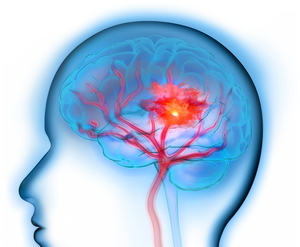

뇌졸중 발생 6개월 이후라도 뇌 구조가 재편돼 상지 운동 기능이 회복될 수 있는 것으로 확인됐다. 가톨릭대 성빈센트병원 재활의학과 유연지 교수팀은 뇌졸중 경험 만성기 환자를 대상으로 대뇌 및 소뇌의 구조적 변화와 상지 운동 기능의 관련성을 분석해 뇌졸중분야 국제학술지(Stroke)에 발표했다.만성기란 병의 진행이 멈췄거나 더디게 진행 중이지만 장기적인 관리, 재활, 돌봄이 필요한 상태를 말한다.뇌졸중 후 신경 회복과 재활 효과는 주로 발병 후 3~6개월 이내인 급성기 및 아급성기에 많이 나타난다고 알려져 있어, 만성기 환자는 재활

외상성 뇌손상 후에는 뇌졸중 위험이 90% 높아지며, 1년 후까지 지속된다는 연구결과가 나왔다.서울대병원 재활의학과(국립교통재활병원 연구소) 이자호 교수·최윤정 연구교수팀은 전국 50세 미만 외상성 뇌손상 환자와 일반인의 뇌졸중 발생 위험을 후향적으로 비교해 미국심장협회지(Journal of the American Heart Association)에 발표했다.외상성 뇌손상은 교통사고와 낙상 등 외부 충격으로 발생하는 뇌 손상이다. 청장년층의 대표적인 사망 원인이자 뇌졸중의 주요 위험 요인 중 하나이다. 경미한 뇌진탕부터 중증인 뇌부